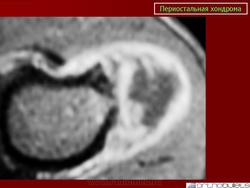

Хондрома периостальная.

Периостальная хондрома (син.: юкстакортикальная хондрома, паростальная хондрома редкая доброкачественная опухоль, состоящая из зрелой хрящевой ткани и расположенная над надкостницей. Обычно она разрушает наружную часть коркового слоя, но не прорастает в костно-мозговой канал. Мужчины болеют в два раза чаще женщин. Типичная локализация - проксимальный конец плечевой и бедренной кости дистальный конец бедренной кости, а также фаланги. В редких случаях одновременно поражается несколько костей. Периостальная хондрома обнаруживается большей частью в метафизарной части, лишь у 30 % больных поражаются диафизы. Опухоль достигает в среднем 2-3 см в диаметре. Она окружена зоной остеосклероза и сопровождается периостальным остеогенезом, так что на границе опухоли с костью образуется грушевидное углубление с четкими контурами. Под микроскопом периостальная хондрома имеет тонкие контуры, она как бы погружена в корковый слой и покрыта надкостницей, как тонкой скорлупой. На разрезе ее ткань синюшно-серая или белая, хрящевые элементы обладают дольчатым строением. Участки обызвествления имеют вид желтовато-белых вкраплений. Эта опухоль состоит из гиалинового хряща, дольки которого разделены фиброзными прослойками или костными балками, местами обызвествленными. Кое-где отмечается проникновение опухолевых клеток в костномозговой канал, на большем же протяжении внутренний контур образован компактной костью.